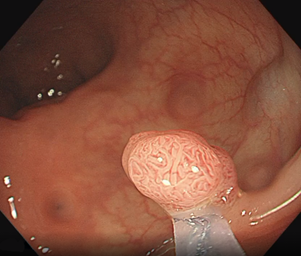

发现和切除是切除息肉最为重要的手段。

然而并不是做过一次切除掉息肉就可以一生无忧,后续还需要根据息肉的性质、大小、数目等决定如何复查。